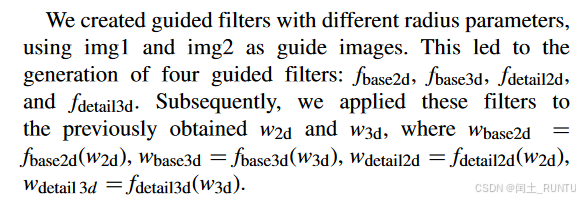

接下来论文表述如下:

此处应该是采用了导向滤波的相关技术,文中提到的guide images我个人理解应该是base image和detail image。产生4个引导滤波器,分别用于之前得到的和

上,得到4个输出结果,其中

和

是基础分量权重,

和

是细节分量权重。

最终结果的基础分量和细节分量计算公式如下: